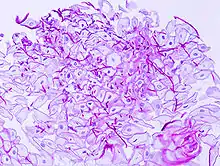

Candidose hyperplasique (pseudo-tumorale)

Elle se manifeste par des plaques hyperkératosiques et bourgeonnantes qui adhérent volontiers à la langue et la muqueuse jugale. Cette forme semble plutôt liée à la consommation tabagique et entraînerait un surrisque de transformation maligne.